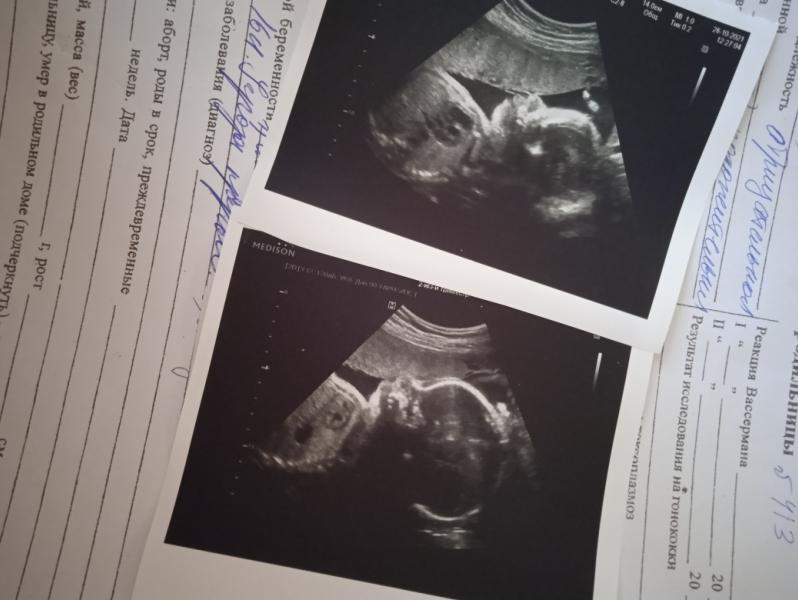

Вот и прошло время беременности, даже пробежало... Завтра уже ехать на плановую госпитализацию.... Хоть нам и поставили месяц назад Сзрп -1й степени, надеюсь что мы просто с папой маленькие и ничего страшного в этом нет, фото конечно старое, 2х месячной давности, но все не на любуюсь)))) скоро мы увидимся с малышкой, надеюсь за месяц вес хорошо набрала, а то была 2300 всего) сумки собраны полностью, последняя уборка дома сегодня будет, а то муж так не справится наверное)) морально пытаюсь подготовиться, но слабо пока получается) живот не опустился еще, тренировочных нет, прям затишье перед бурей 😀